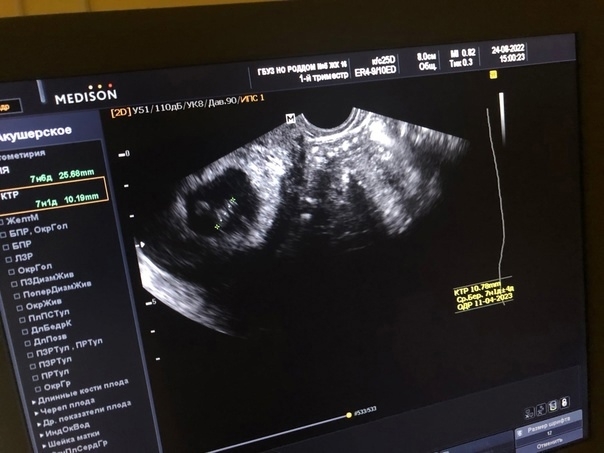

Первое УЗИ при беременности: 7 недель, дата 24.08.2022, как я узнала о беременности!

Моё самое первое УЗИ.

Я узнала в этот день, что я все таки беременна. Нам 7 недель.

24.08.2022 ты растешь, крошка 💗💗💗